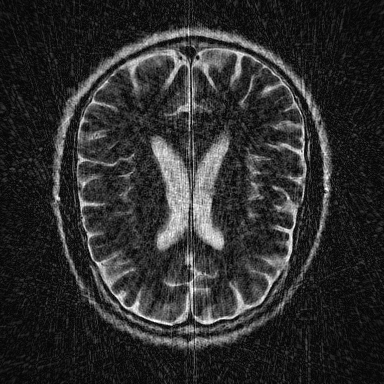

This article presents a novel undersampled magnetic resonance imaging (MRI) technique that leverages the concept of Neural Radiance Field (NeRF). With radial undersampling, the corresponding imaging problem can be reformulated into an image modeling task from sparse-view rendered data; therefore, a high dimensional MR image is obtainable from undersampled $k$-space data by taking advantage of implicit neural representation. A multi-layer perceptron, which is designed to output an image intensity from a spatial coordinate, learns the MR physics-driven rendering relation between given measurement data and desired image. Effective undersampling strategies for high-quality neural representation are investigated. The proposed method serves two benefits: (i) The learning is based fully on single undersampled $k$-space data, not a bunch of measured data and target image sets. It can be used potentially for diagnostic MR imaging, such as fetal MRI, where data acquisition is relatively rare or limited against diversity of clinical images while undersampled reconstruction is highly demanded. (ii) A reconstructed MR image is a scan-specific representation highly adaptive to the given $k$-space measurement. Numerous experiments validate the feasibility and capability of the proposed approach.